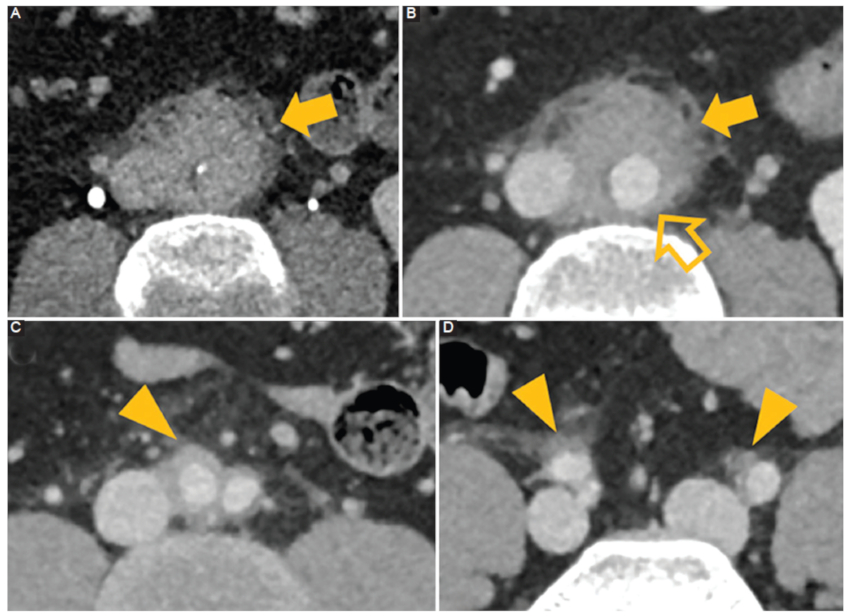

Figura 7

Mediólisis arterial segmentaria. Hombre de 38 años con pancreatitis aguda. A: la ecografía muestra un diámetro aumentado de la arteria hepática común y esplénica con material ecogénico que ocupa parcialmente el lumen (flecha). B: TC con contraste corte axial. Se identifica una estenosis secundaria a un trombo en la arteria hepática (flecha) asociado a colgajos de disección en el tronco celíaco (flecha hueca) y la arteria esplénica (cabeza de flecha). C: TC con contraste corte axial. Disección de la arteria mesentérica superior (cabeza de flecha hueca). D: TC con contraste corte axial. Estenosis, disección y presencia de trombos en ambas arterias renales (flecha) asociado a defectos de perfusión (flechas huecas). E: TC con contraste corte axial. Disección de la arteria esplénica (punta de flecha) con un defecto de perfusión (asterisco).